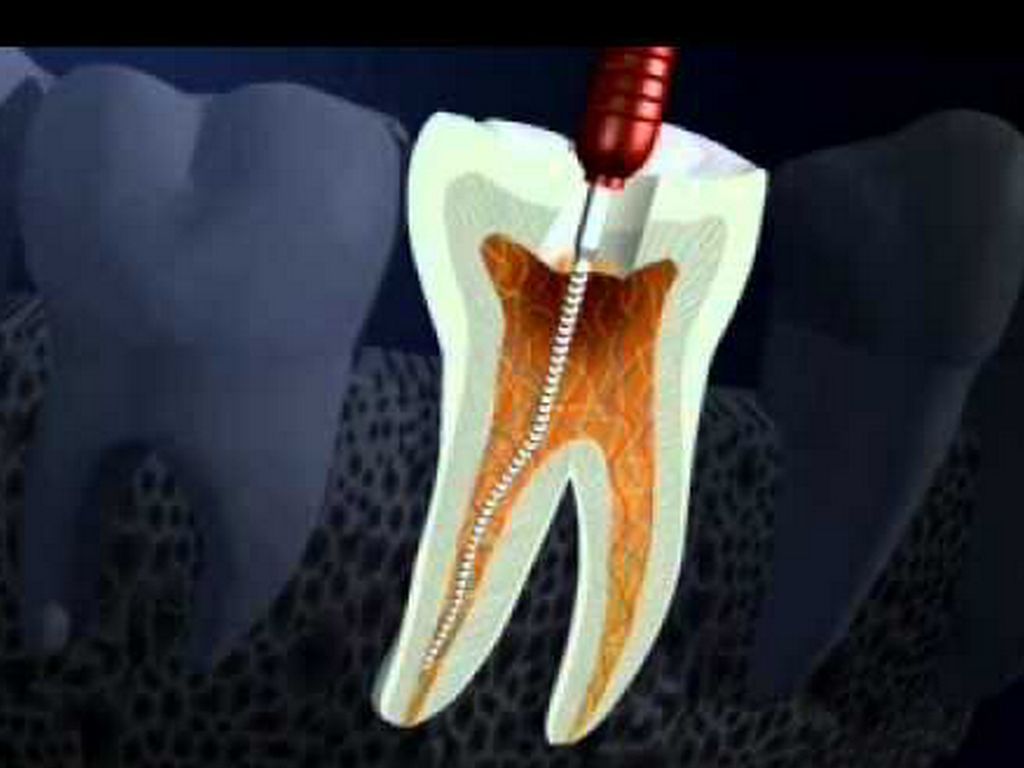

LIMPIEZA Y CONFORMACIÓN

Remoción del techo de cámara pulpar

Identificación del piso pulpar y entrada de conductos

Instrumentación de los conductos